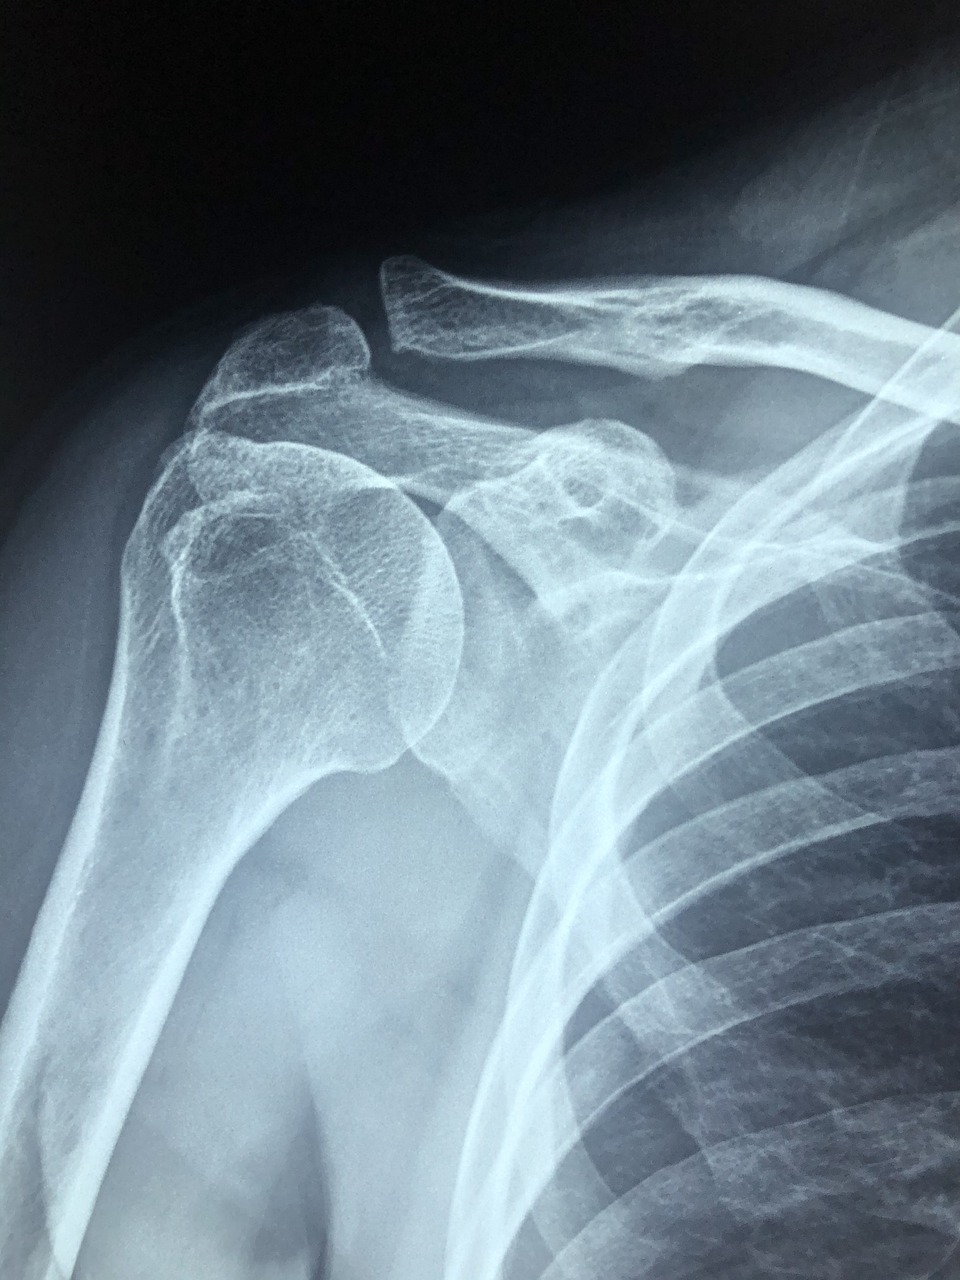

퇴행성 어깨 관절염 완치가 가능할까?

퇴행성 어깨 관절염 이란 무엇이고 어떻게 치료할 수 있을까요? 방법을 알아보기전에 오십견에 대해서 알아보겠습니다.

오십견이란 50대 전후를 가르키는 명칭입니다. 정식 진단명 으로는 "유착성 관절낭염" 이라고 합니다.

노화로 인한 퇴행성 변화가 가장 큰 원인이라고 볼 수 있겠습니다.